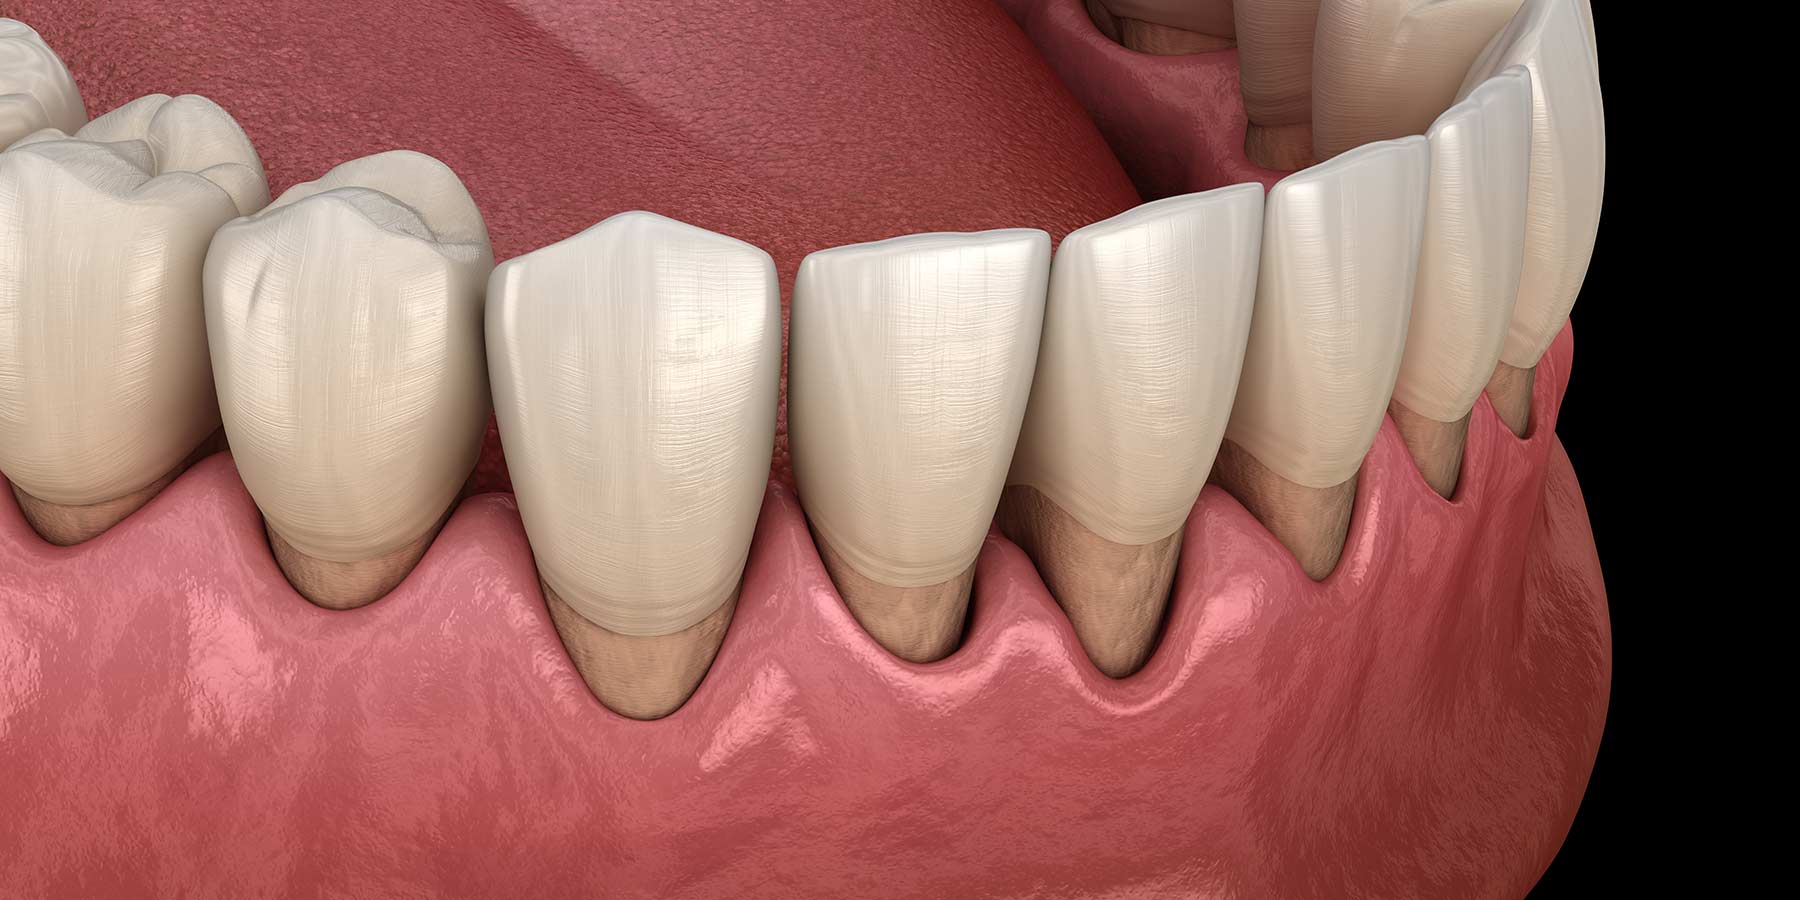

Parodontopatija predstavlja hronično oboljenje koje se sreće kod 90% ljudi u manjem ili većem obliku. Ovo oboljenje zahvata potporni aparat zuba, odnosno desni, ligamente i kost koja pomaže zubu da bude učvršćen.

Parodontopatija kao takva prolazi kroz nekoliko faza, a prva je gingivitis, odnosno upala desni. U ovoj fazi je dovoljno ukloniti kamenac i meke naslage kako bi se upala smirila.

Kako oboljenje napreduje, stvara se sve više parodontalnih džepova, i nestaje sve više kosti oko zuba, čime oni postaju skloni rasklimavanju. Da do toga ne bi došlo, moramo pristupiti obradi tih parodontalnih džepova, bilo kiretažom ili njihovom hirurškom obradom.

U poslednjoj fazi terapije moramo uzeti nož u ruke. U ovom slučaju je to mali nož, skalpel, kojim pravimo nekoliko kratkih rezova oko zuba koje želimo sačuvati. Oko ovih zuba se najčešće nalaze veliki parodontalni džepovi, koji predstavljaju sklonište za bakterije i sav infektivni sadržaj koji razara kost oko zuba.

Kada jasno vidimo, možemo odlučiti koja kost je dobra, a koja se mora ukloniti zajedno sa inficiranim tkivom.

Nakon što smo sve uklonili, dodajemo veštačke kosti i ušivamo desni na prvobitno mesto, kako bismo dali vremena kosti da zaraste i pruži potporu zubima.

Cilj ove operacije je sprečvanje napredovanja oboljenja i smanjenje dubina parodontalnih džepova. Takođe, može se očekivati i smanjenje pomeranja pojedinih zuba. Međutim, ukoliko se navike ne promene i dođe do ponovnog nakupljanja plaka i kamenca na zubima, rezultati će biti minimalni ili nepostojeći.